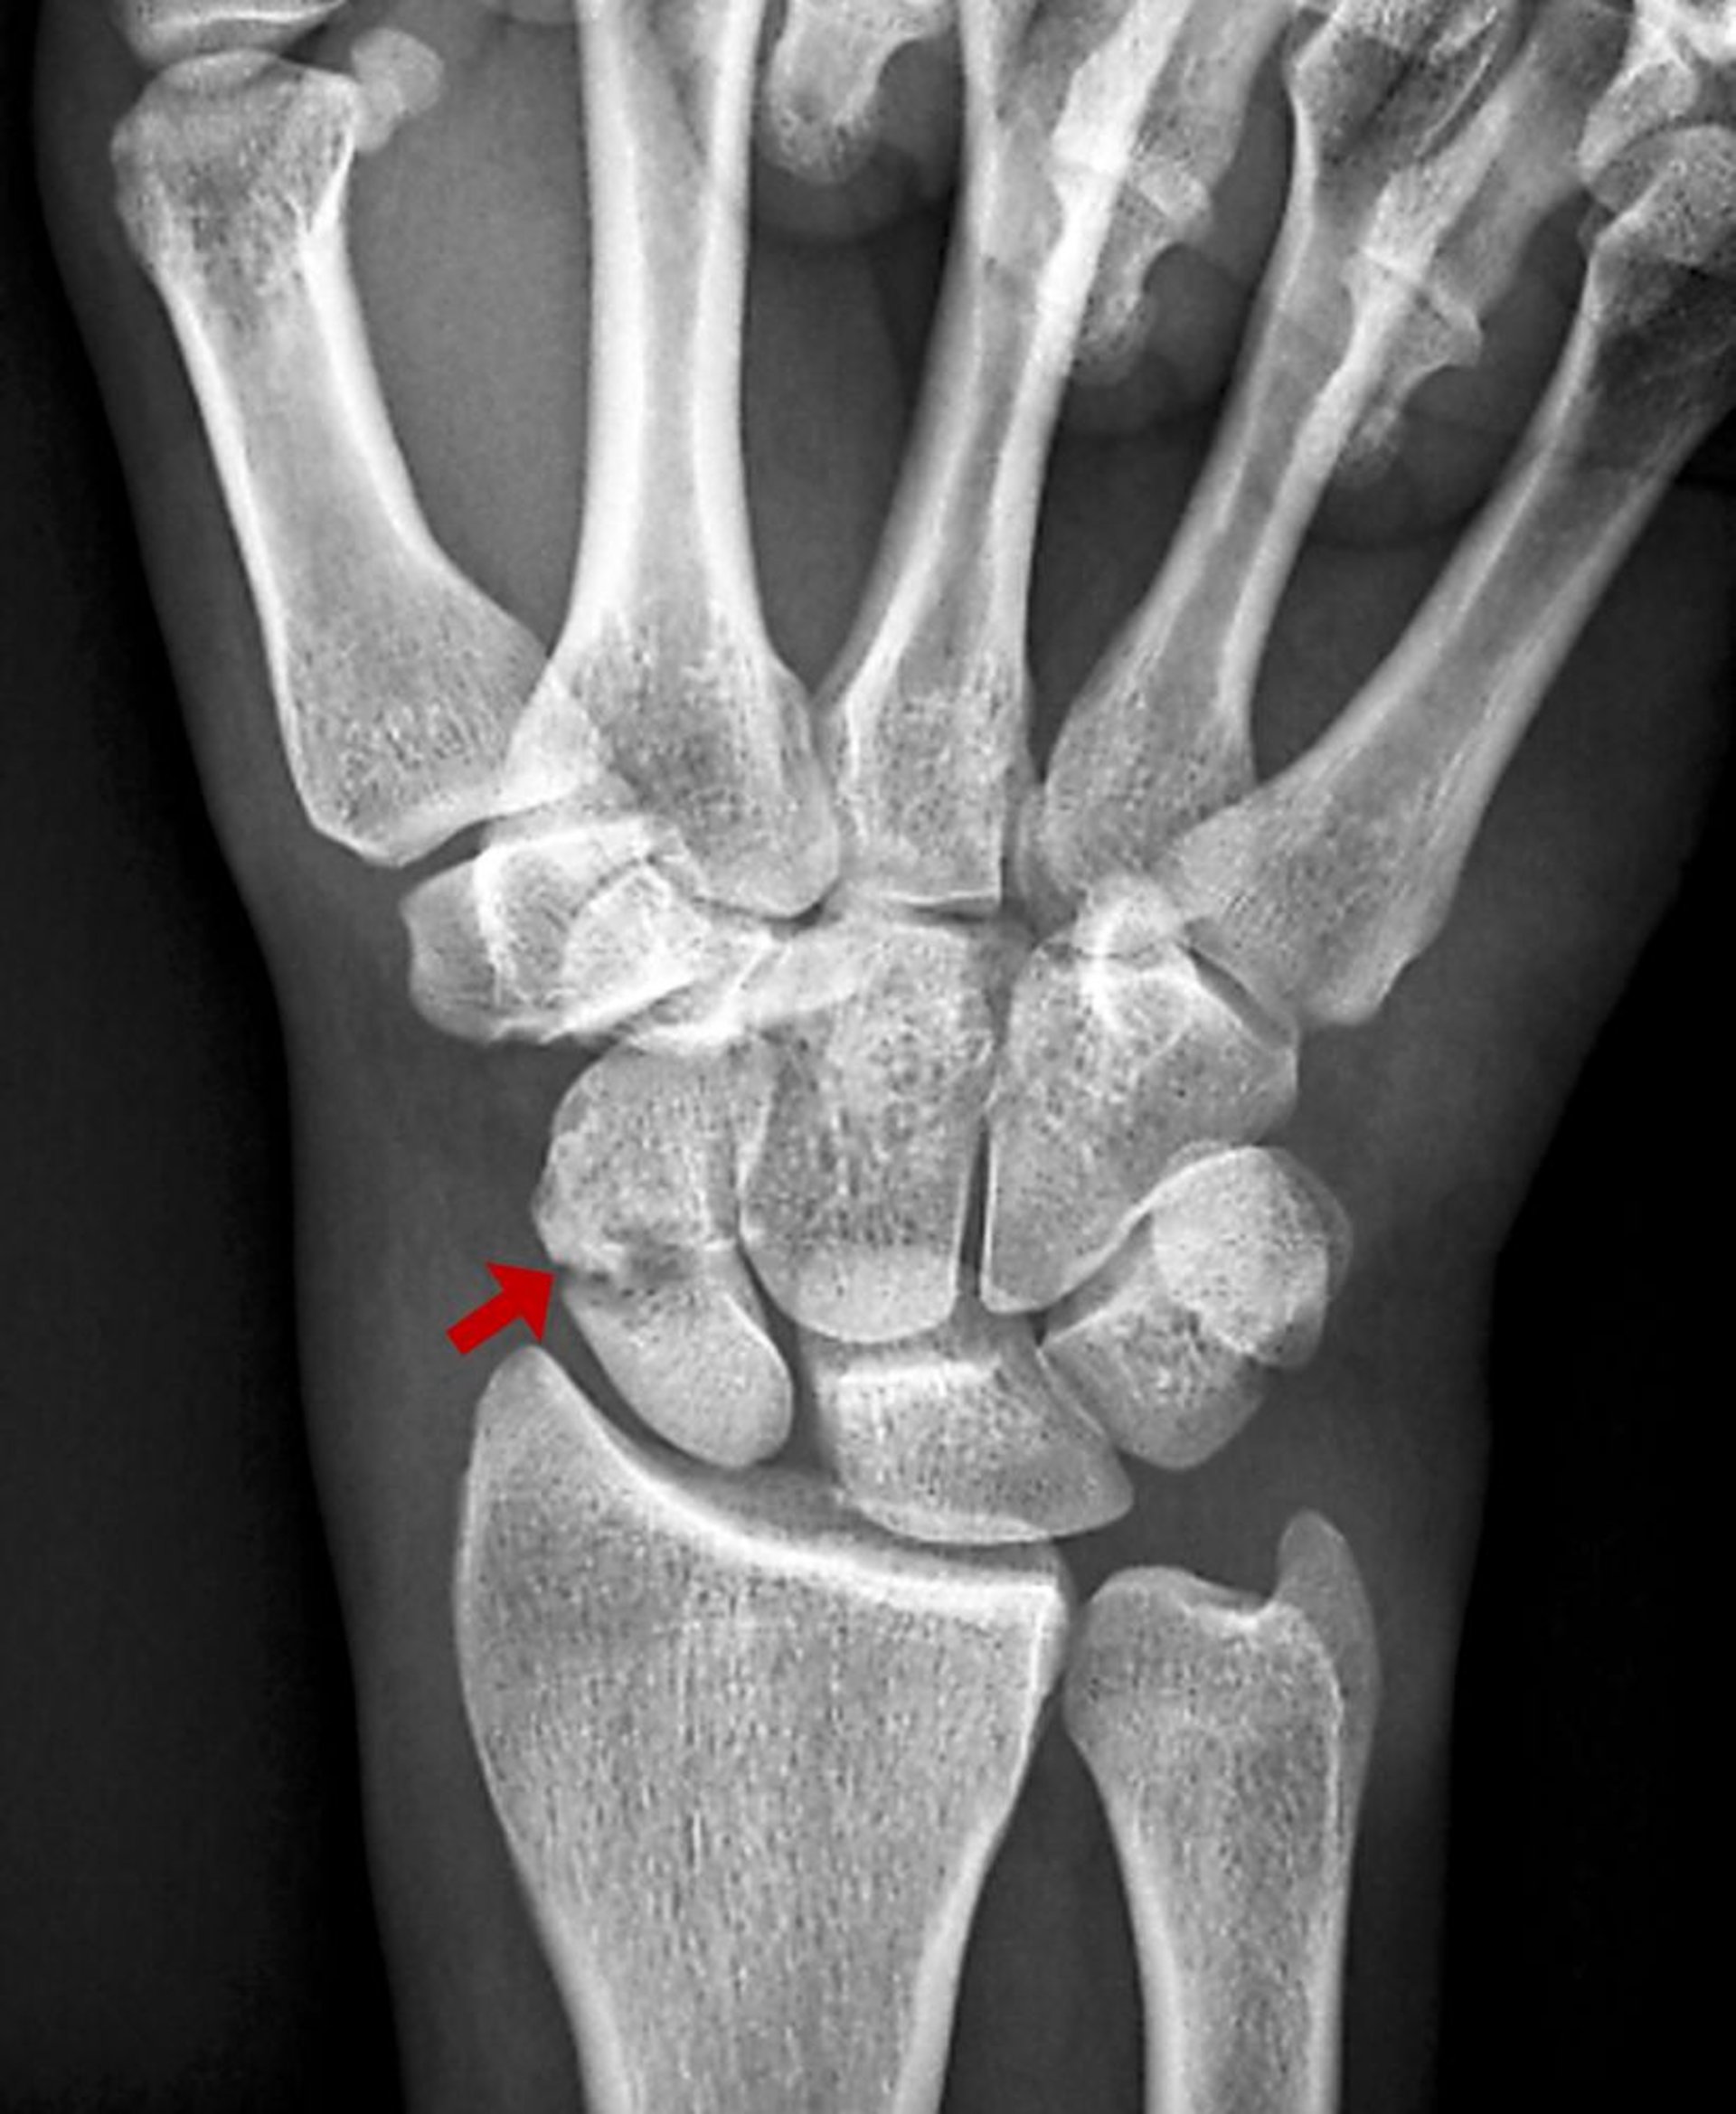

Fracturas del escafoides (navicular)

Las fracturas escafoides suelen ser el resultado de hiperextensión de la muñeca. Puede que no sean visibles en las radiografías iniciales. Las complicaciones pueden ser significativas.

El escafoides es el hueso carpiano más comúnmente lesionado. Las fracturas del escafoides suelen ser el resultado de una hiperextensión de la muñeca, en general durante una caída sobre una mano hiperextendida. Pueden interrumpir el suministro de sangre al escafoides proximal. La osteonecrosis es por lo tanto una complicación frecuente, incluso cuando el cuidado inicial es óptimo, y puede producir una artritis degenerativa incapacitante de la muñeca.

Inicialmente, se toman radiografías simples (vistas anteroposterior, lateral y oblicuas), pero suelen ser normales. Solo alrededor del 70% de las fracturas del escafoides se observan en las radiografías iniciales (1).